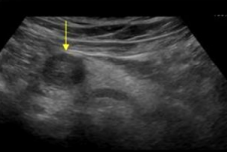

Describe this image

Differential dx?

A well-defined, solid, round, hypoechoic mass located in the head of the pancreas. Most likely adenocarcinoma but needs to be confirmed with biopsy